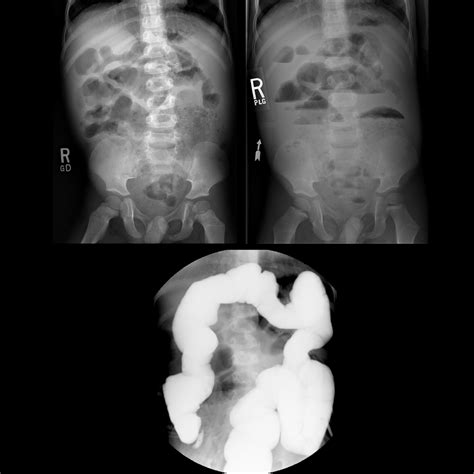

• X-rays: Often the first line of defense for bone fractures or lung issues.

• Fluoroscopy: Used to observe real-time movement, such as how a child swallows or how the gastrointestinal tract functions.

X-ray Minimal Bone fractures, pneumonia, chest congestion